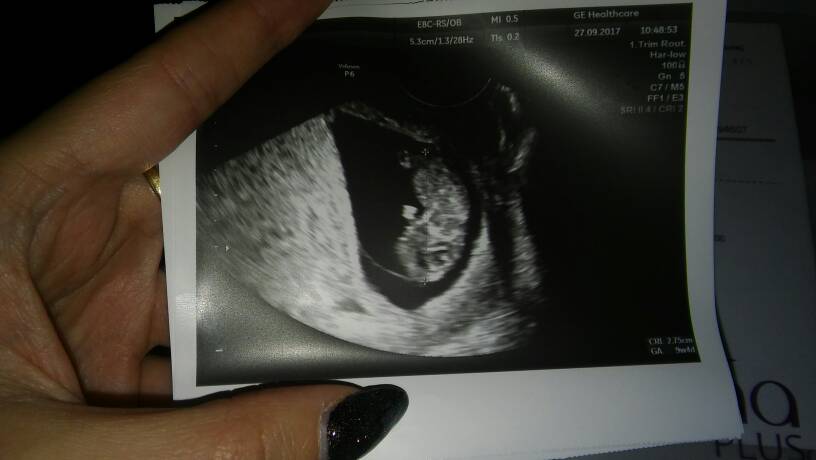

Twój gin ma lepsze usg moje jakieś słabeZobacz załącznik 824676

Tak wiec wizyta z 29.09 - gdy mój bobasek miał 13 t 2d.

Ktos dopatrzył sie ze ssie kciuk![]()